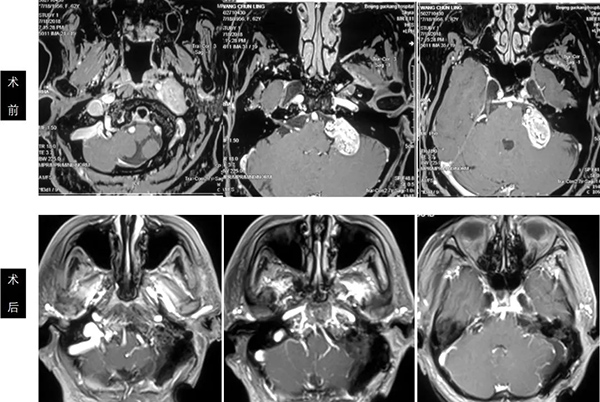

岩斜脑膜瘤手术前后

枕骨大孔脑膜瘤手术前后